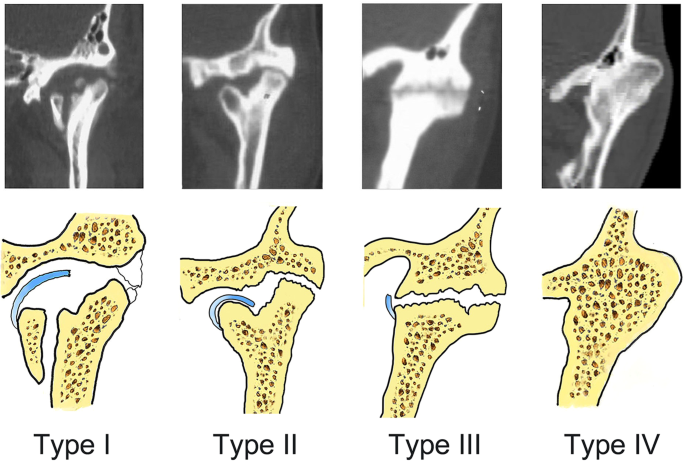

TMJ ankylosis is caused by a variety of conditions such as local or systemic infections, TMJ arthritis, trauma, and neoplasm. The most common etiology of TMJ ankylosis is previous trauma, with the second being infection [3, 10].